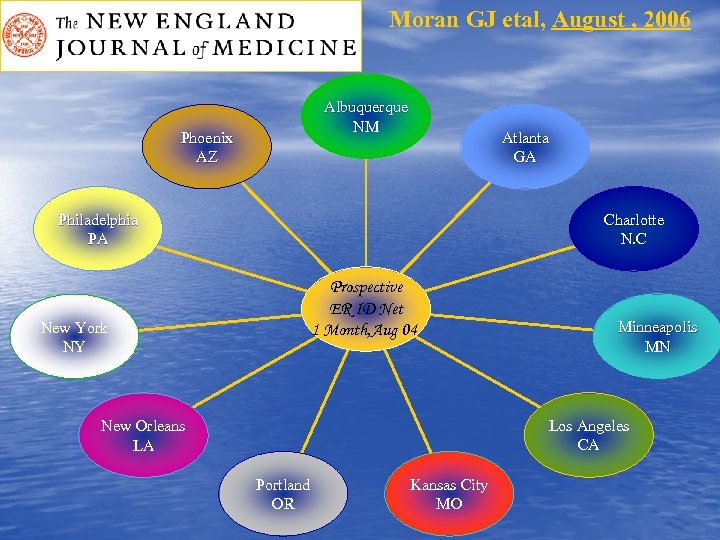

Moran GJ etal, August , 2006 Albuquerque NM Phoenix AZ Atlanta GA Philadelphia PA Charlotte N. C Prospective ER ID Net 1 Month, Aug 04 New York NY Minneapolis MN Los Angeles CA New Orleans LA Portland OR Kansas City MO

Moran GJ etal, August , 2006 Albuquerque NM Phoenix AZ Atlanta GA Philadelphia PA Charlotte N. C Prospective ER ID Net 1 Month, Aug 04 New York NY Minneapolis MN Los Angeles CA New Orleans LA Portland OR Kansas City MO